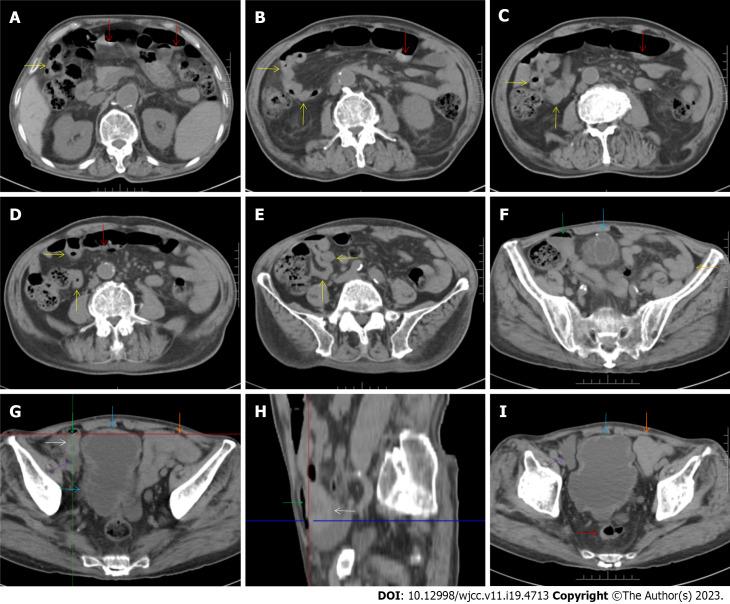

A 72-year-old male patient was definitively diagnosed with MDS with excess blasts-1 (MDS-EB-1) based on an increase in the percentages of myeloblasts and cluster of differentiation (CD)34+ hematopoietic progenitors and the identification of myeloid neoplasm-associated somatic mutations in bone marrow samples. The patient was treated with hypomethylation therapy and was able to maintain a steady disease state for 2 years. In the treatment process, the advanced MDS patient experienced an episode of progressive pancytopenia and bone marrow aplasia. During the aplastic crisis, the bone marrow was infiltrated with sparsely distributed atypical lymphocytes. Surprisingly, the leukemic cells disappeared. Immunological analysis revealed that the atypical lymphocytes expressed a high frequency of CD3, CD5, CD8, CD16, CD56 and CD57, suggesting the activation of autoimmune cytotoxic T-lymphocytes and natural killer (NK)/NKT cells that suppressed both normal and leukemic hematopoiesis. Elevated serum levels of inflammatory cytokines, including interleukin (IL)-6, interferon-gamma (IFN-γ) and tumor necrosis factor-alpha (TNF-α), confirmed the deranged type I immune responses. This morphological and immunological signature led to the diagnosis of severe aplastic anemia secondary to large granule lymphocyte leukemia. Disseminated tuberculosis was suspected upon radiological examinations in the search for an inflammatory niche. Antituberculosis treatment led to reversion of the aplastic crisis, disappearance of the atypical lymphocytes, increased marrow cellularity and 2 mo of hematological remission, providing strong evidence that disseminated tuberculosis was responsible for the development of the aplastic crisis, the regression of leukemic cells and the activation of CD56+ atypical lymphocytes. Reinstitution of hypomethylation therapy in the following 19 mo allowed the patient to maintain a steady disease state. However, the patient transformed the disease phenotype into acute myeloid leukemia and eventually died of disease progression and an overwhelming infectious episode.

一名72岁男性患者,基于骨髓样本中原始粒细胞和分化簇(CD)34+造血祖细胞百分比增加以及髓系肿瘤相关体细胞突变的鉴定,被明确诊断为伴有过多原始细胞-1的骨髓增生异常综合征(MDS-EB-1)。该患者接受了低甲基化治疗,并能够维持稳定的疾病状态2年。在治疗过程中,这位晚期MDS患者经历了一次进行性全血细胞减少和骨髓再生障碍。在再生障碍危象期间,骨髓中浸润有散在分布的非典型淋巴细胞。令人惊讶的是,白血病细胞消失了。免疫分析显示,这些非典型淋巴细胞高表达CD3、CD5、CD8、CD16、CD56和CD57,提示自身免疫性细胞毒性T淋巴细胞和自然杀伤(NK)/自然杀伤T(NKT)细胞激活,抑制了正常和白血病造血。包括白细胞介素(IL)-6、干扰素-γ(IFN-γ)和肿瘤坏死因子-α(TNF-α)在内的血清炎性细胞因子水平升高,证实了紊乱的I型免疫反应。这种形态学和免疫学特征导致诊断为继发于大颗粒淋巴细胞白血病的严重再生障碍性贫血。在寻找炎症病灶的放射学检查中怀疑有播散性结核病。抗结核治疗导致再生障碍危象逆转、非典型淋巴细胞消失、骨髓细胞数量增加以及2个月的血液学缓解,有力地证明了播散性结核病是再生障碍危象发生、白血病细胞消退和CD56+非典型淋巴细胞激活的原因。在接下来的19个月中重新进行低甲基化治疗使患者能够维持稳定的疾病状态。然而,患者疾病表型转变为急性髓系白血病,最终死于疾病进展和严重感染发作。